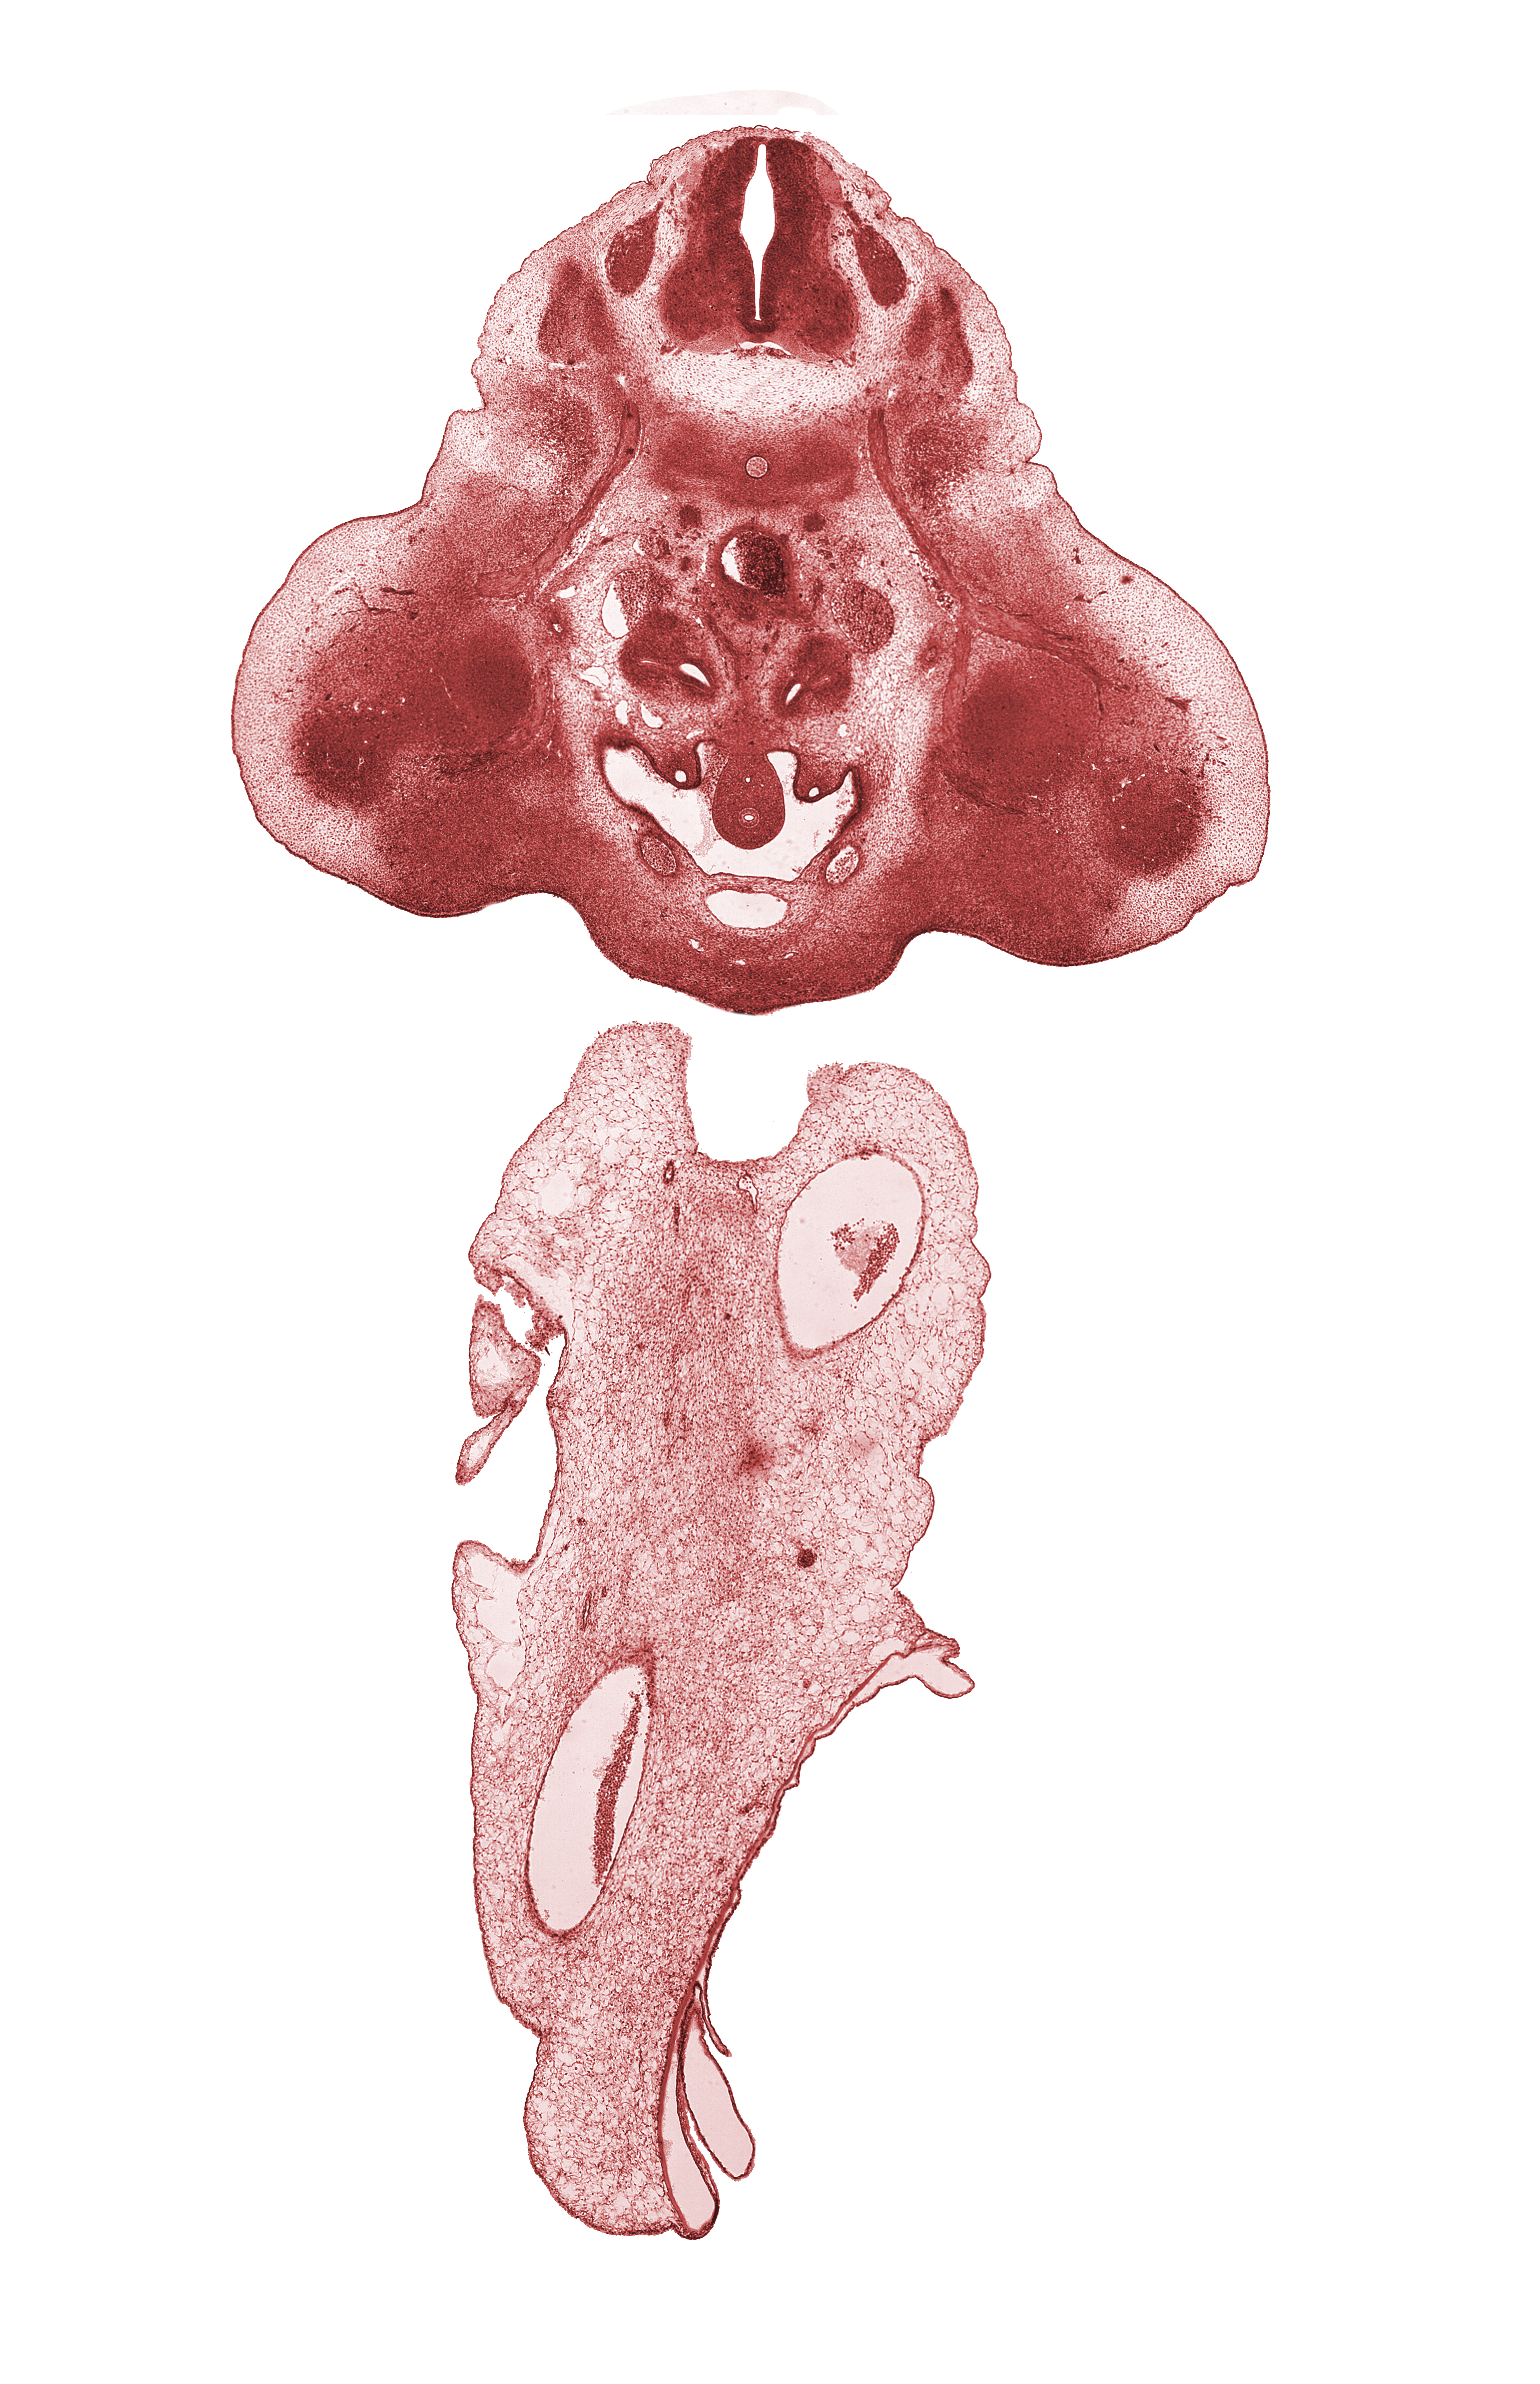

Carnegie Embryo #6520 | Location: 26-01-05

Keywords: L-2 spinal ganglion, L-3 spinal nerve, hindgut, mesonephric duct, neural arch, pelvis of kidney (metanephros), peritoneal cavity, postcardinal vein, sympathetic trunk, urinary bladder (vesico-urethral canal)

Source: The Virtual Human Embryo.